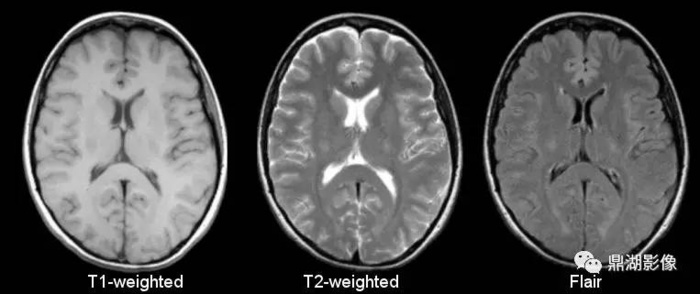

1.TIWI、T2WI

作为磁共振检查最基础的序列,T1WI、T2WI不可缺少。上学的时候我们就说:T1看解剖,T2看病变。到底什么意思呢?我们看下面这两幅图

右侧T1WI:图像的整体感官跟“临床图像”的“习惯配色风格”非常接近,你看白质是白的,灰质是灰的,脑脊液是黑的。

左侧T2WI:我想不用说了吧,不会看磁共振的人都知道,这白白亮亮的是病变。

2.Flair序列(黑水序列)

FLAIR是fluid attenuated inversion recovery的英文缩写,在脑、脊髓MRI(核磁共振)中常用。在T2WI中可抑制脑脊液的高信号,使邻近脑脊液、具有高信号(长T2)的病变得以显示清楚。FLAIR序列属于反转恢复序列(inversion recovery,IR),IR序列是属于获得MRI图像的技术中的序列技术。

T2 FLAIR可以区分游离水与结合水:

在T2 FLAIR序列,游离水呈低信号,如:

而结合水呈高信号,如:

T2 FLAIR能更清楚显示在常规T2WI被脑脊液高信号掩盖的病变,尤其在脑室周围、脑表面、蛛网膜下腔区域,提高诊断的敏感性。